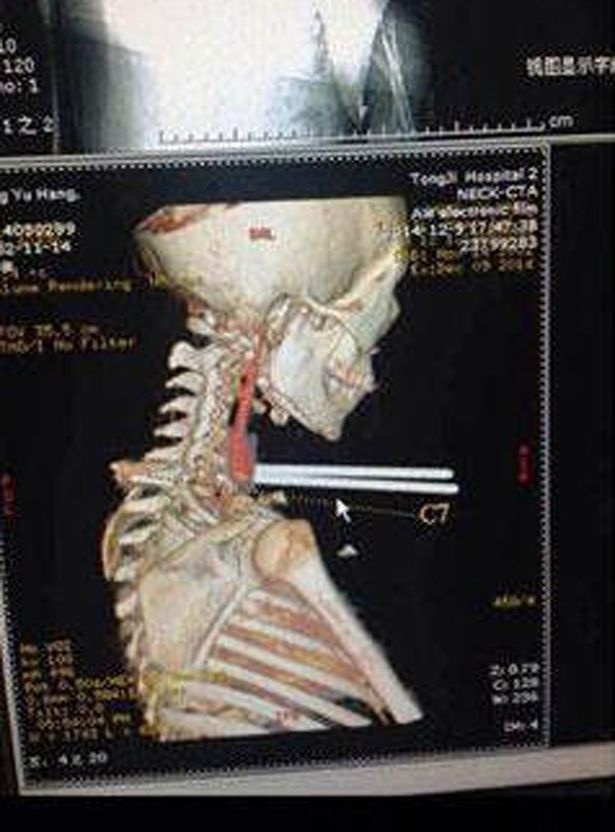

| Tấm ảnh chụp X quang cho thấy đôi đũa không đâm trúng bất kỳ cơ quan nào trong cơ thể Jun Chia. Ảnh: Mirror |

"Đôi đũa không đâm trúng khí quản, thực quản và các mạch máu chính của nạn nhân. Cậy ấy rất may mắn. Sau đó chúng tôi đã phẫu thuật để lấy đôi đũa", Zhou Jen, một bác sĩ, kể.